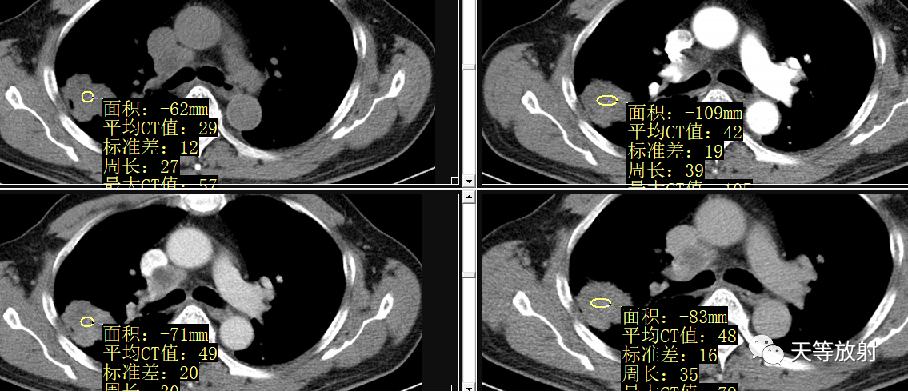

动脉期强化峰值很高,静脉及延迟期维持较高强化。

2bfbbb11f015f44e7a146d7236a034fa.png